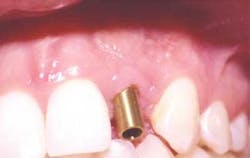

GingiHue™ Posts (Implant Innovations, Inc.) are titanium abutments manufactured with a gold-nitride (TiN) coating. The TiN coating is created with a plasma coating process in which titanium and nitrogen ions are combined. These molecules are bonded to the titanium GingiHue Posts. The gold color provides increased "warmth" to the implant site by eliminating the gray metallic colors associated with titanium abutments (Figure 3, below). The GingiHue Post is attached to the implant with a Gold-Tite Abutment Screw that is tightened to 35Ncm of torque with a restorative torque indicator. When the appropriate torque is applied to the Gold-Tite Abutment Screw, the screw achieves 75 percent greater pre-load than conventional abutment screws. This results in a reduced propensity for screw loosening, screw breakage, and subsequent restorative failure.

null